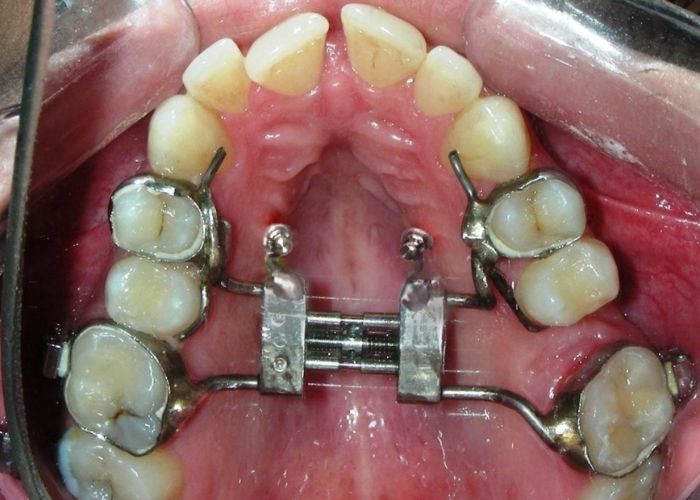

Was installed a Hyrax-type 10mm palatal expander of the Brazilian trademark Morelli® , modified by the author to be adapted to receive TADs microscrews, in order to initiate maxillary disjunction with MARPE (Mini-implant Assisted Rapid Palatal Expansion), TADS was installed with skeletal anchorage placed bilaterally having as references the roots of the maxillary canines and first premolars. Prior to insertion, local infiltrative anesthesia was administered using 2% lidocaine hydrochloride with 1:100,000 epinephrine. A total dose of approximately 0,8 mL per side (cortical infiltration technique). The TADs were inserted under aseptic conditions using a manual driver. Microscrew Evolution 1,6 Ø x 10 mm from the Argentine brand Odontit® . The Hyrax expander was then fitted and activated after 48 hrs .

Protocol of one activation per day was followed for a period of three weeks where the first clinical and radiographic evaluation was performed, showing clear signs of skeletal expansion, including the presence of a midline diastema. One more week of activations was added with a total of 28. The patient reported moderate headache during the first week of activation.

Having successfully achieved the expansion, we proceed to the intrusion of the posterior superior sectors, modifying the Hyrax by adding anchoring hooks at the buccal level of the first premolars. Using the Hyrax as anchorage, we sought a parallel intrusion. This could be replaced by a palatal bar. TADs were installed bilaterally at the mesial level of the first molars, inserting them as parallel as possible to the roots.